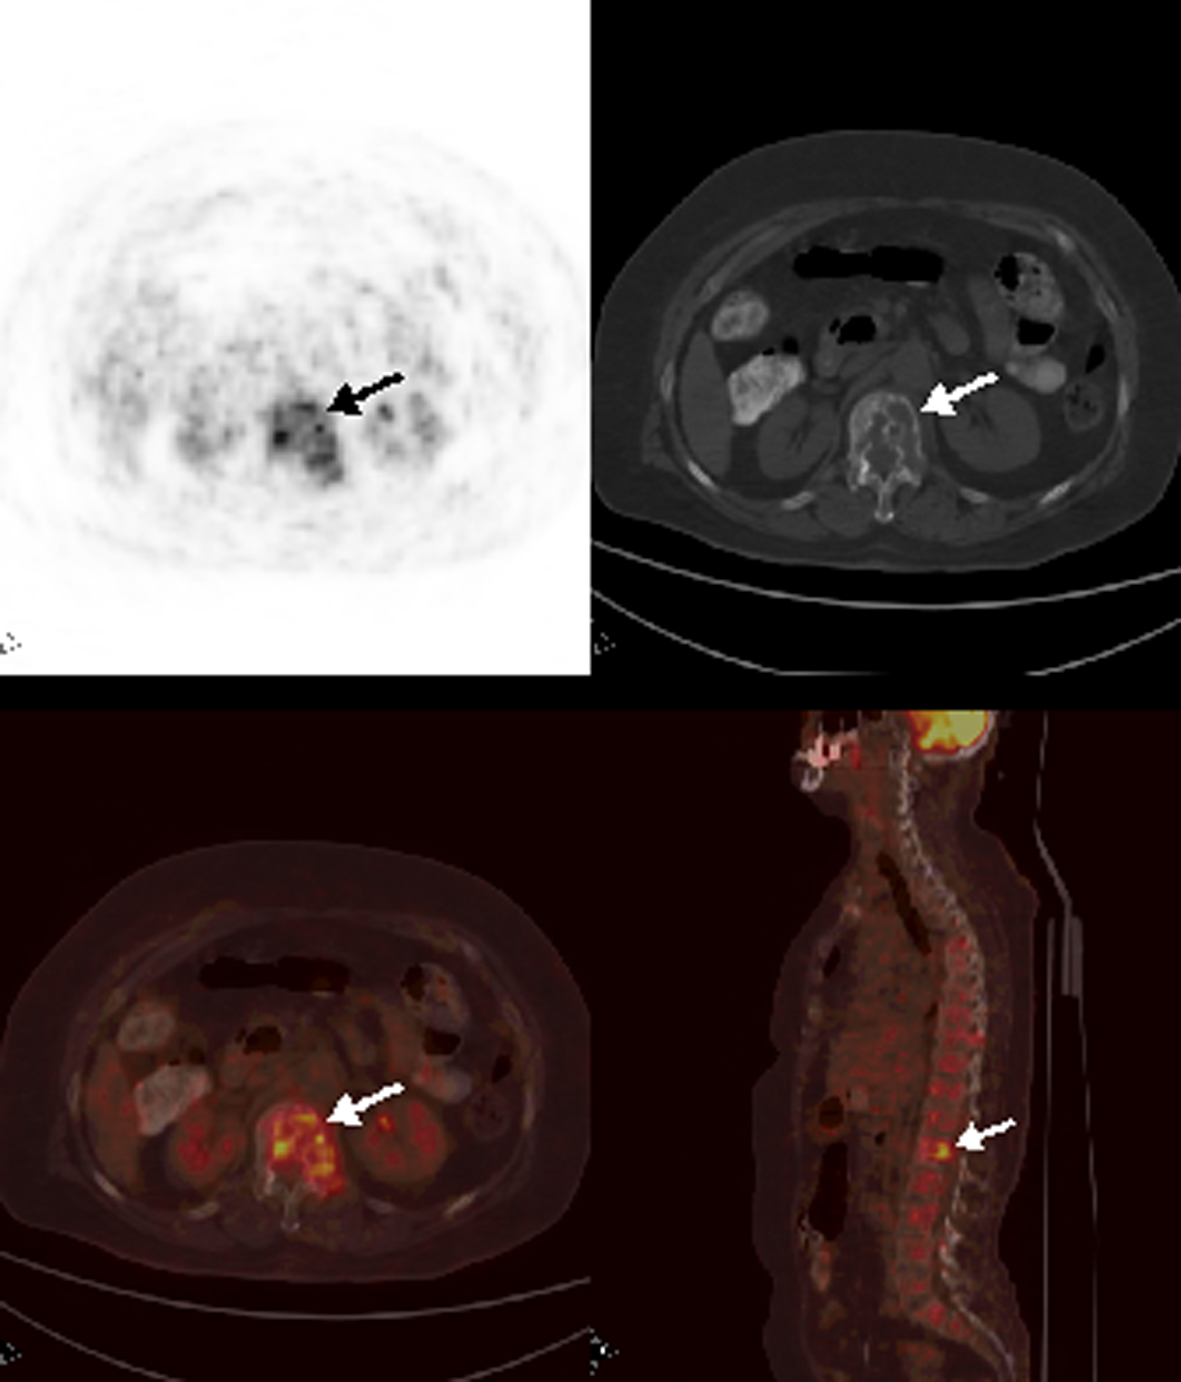

Patient 8

A 69-year-old woman with nasopharyngeal cancer was referred to PET/CT in order to detect a suspected local recurrence. FDG PET/CT images demonstrated increased FDG uptake at the left nasopharyngeal region suggestive of locally recurrent tumor (Fig. 4). Also, there were multiple bone and bone marrow involvement at the vertebral column and manubrium sterni. Bone marrow biopsy proved sinonasal tumor involvement despite a thrombocyte count of 180,000 per µL.

![]() Click for large image | Figure 4. Axial and sagittal PET/CT images depicted multiple heterogeneously increased FDG uptake at vertebral column. |